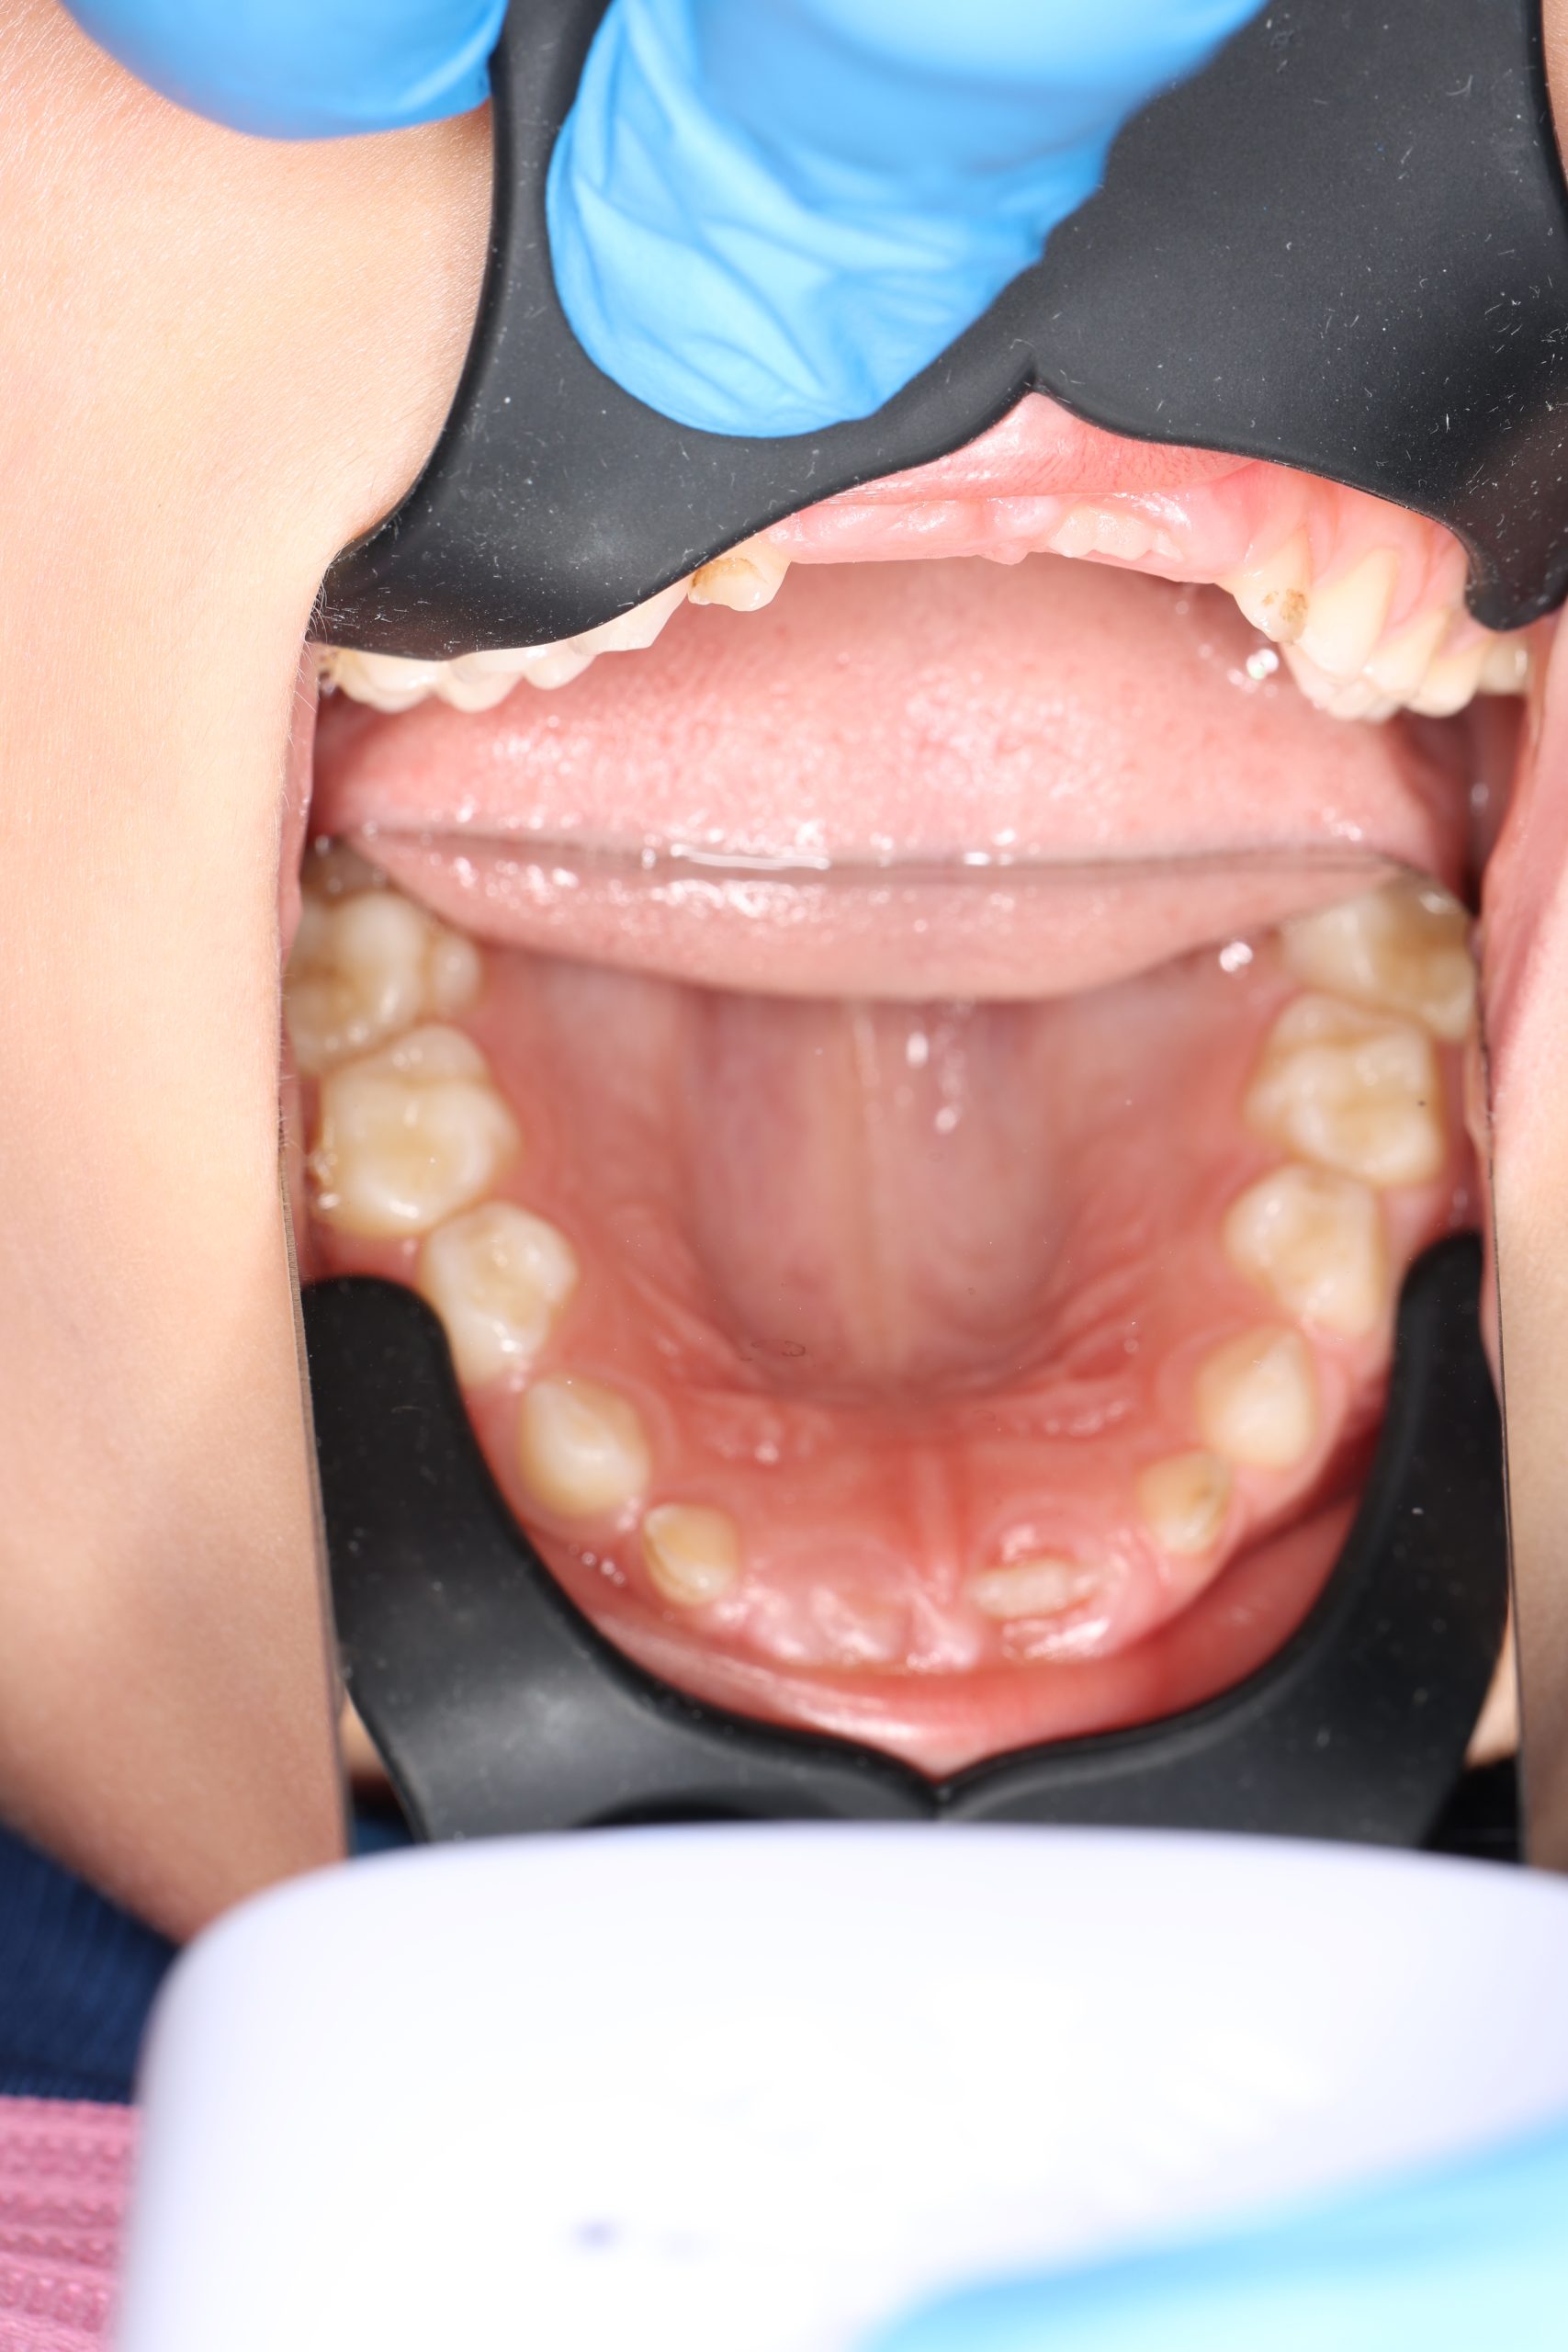

Together with your child, we practice brushing techniques, correct mistakes, and provide personalized recommendations. We advise whether to use manual or electric brushes, floss, interdental brushes, or remineralizing gels. - Plaque Removal with AIRFLOW Prophylaxis Master (EMS, Switzerland)

From age 4–5 and up, we perform full GBT cleaning using an ultra-fine erythritol powder to clean even hard-to-reach areas gently and safely. It does not damage enamel and is ideal even around braces — no need to remove brackets or wires. - Tartar Removal (If Needed)